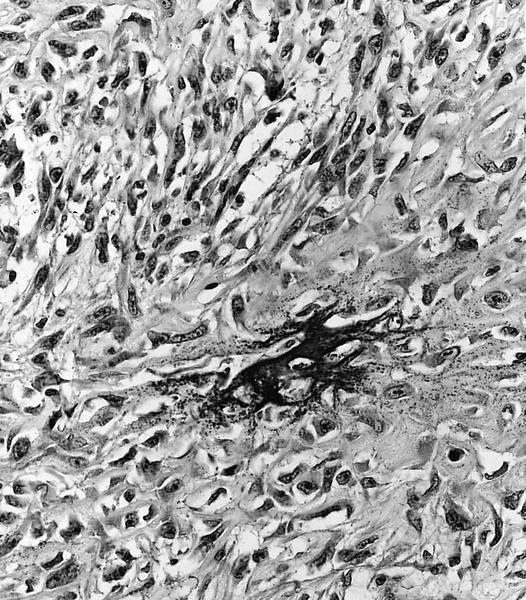

- Parosteal osteosarcoma:

- Invasion: tumor invades soft tissue; 25% invade bone (cortex / medullary)

- Neoplastic cells: fibroblast-like spindle cells (minimal atypia); between bony trabeculae (may be hypocellular)

- Scattered mitoses may be seen

- Neoplastic bone: parallel bony trabeculae (osteoblastic rimming may be present)

- Cartilage (present in ~50% of cases):

- Nodules within lesion (hypercellular)

- Cartilage cap: partially overlays tumor (moderate cellularity, chondrocytes are not arranged in columns, mild to moderate atypia)

- Dedifferentiation (15 - 25% of cases): abrupt transition to high grade sarcoma

Microscopic (histologic) images

Contributed by Jesse Hart, D.O., Borislav A. Alexiev, M.D. and AFIP